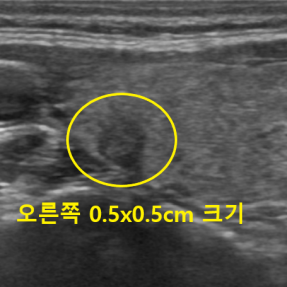

유방암 · 갑상선암 진단사례

Thyroid Clinic

정확한 검사와 해석으로 건강한 일상을 되돌려드립니다.